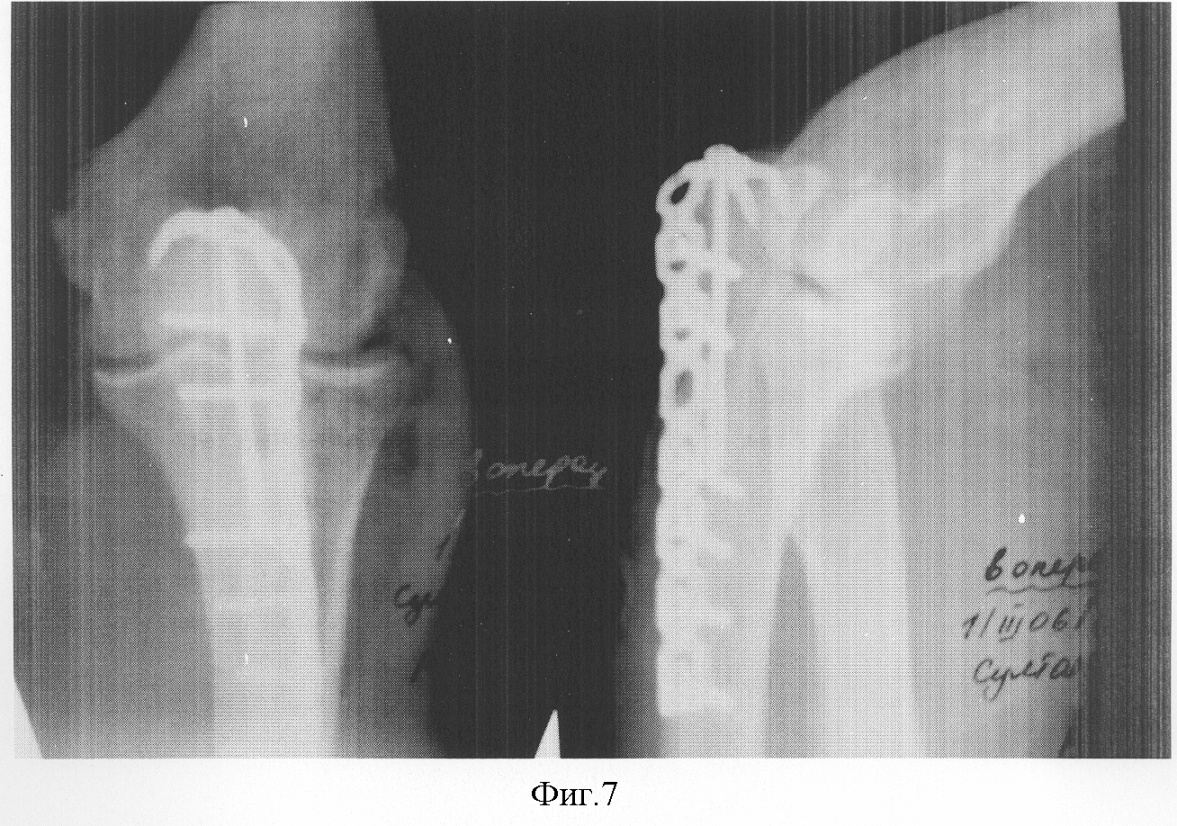

На фиг.7 изображена рентгенограмма оперированного перелома локтевого отростка с применение стабильного накостного остеосинтеза отмоделированной реконструктивной пластиной.

Больной С., 45 лет, 26.02.2006 г. доставлен в МУ ГТВВ г.Уфы через 2 часа после бытовой травмы, полученной в результате падения на правый локоть с диагнозом: оскольчатый внутрисуставной перелом локтевого отростка правого предплечья со смещением отломков. При поступлении блокада перелома новокаином, иммобилизация локтевого сустава прямой гипсовой лангетой. Проводилась подготовка к операции. При неосложненном течении травмы 1.03.2006 г., то есть на 5-е сутки, открытая репозиция, накостный металлоостеосинтез локтевого отростка правого предплечья реконструктивной пластиной, которая отмоделирована по форме в процессе предоперационного планирования на основании дооперационных рентгеновских снимков.

Ход операции. После обработки операционного поля через продольный линейный разрез 10 см, соответствующий заднему краю локтевой кости и наружному краю локтевого отростка, скелетизировали наружную поверхность локтевой кости и локтевого отростка. Через верхушку локтевого отростка в диафиз локтевой кости провели 2 спицы Киршнера диаметром 1,8 мм по оси локтевой кости. Между интраоперационными спицами, верхушкой локтевого отростка и трехглавой мышцей правого плеча провели загнутый конец пластины, уложили штыкообразную часть на внутреннюю поверхность локтевого отростка, а прямую ее часть – по наружной поверхности локтевой кости. Используя интраоперационные спицы в качестве направляющей после репозиции промежуточных отломков, произвели дозированную компрессию отломков по длине и ширине короткорезьбовым спонгиозным шурупом, проведенным через отверстие пластины, соответствующее верхушке локтевого отростка, в диафиз локтевой кости. После контроля стояния отломков по окончании компрессии пластину зафиксировали к наружной поверхности локтевой кости бикортикальными шурупами. Провели бикортикальные шурупы через пластину для фиксации крупных отломков локтевого отростка. Удалили спицы Киршнера, провели послойные швы на рану, наложили асептическую повязку. Осуществили рентген-контроль.

Получен стабильный функциональный металлосинтез с хорошим анатомическим стоянием отломков. С первых суток после операции начата лечебная физкультура, проводились перевязки, симптоматическое лечение. Неосложненный послеоперационный период. Послеоперационная рана зажила per prim. К моменту снятия швов полностью восстановлена функция травмированного сустава, больной выписан из стационара к труду – работе водителя автомашины.